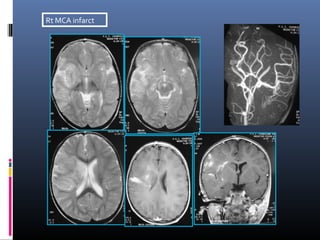

Rt MCA infarct